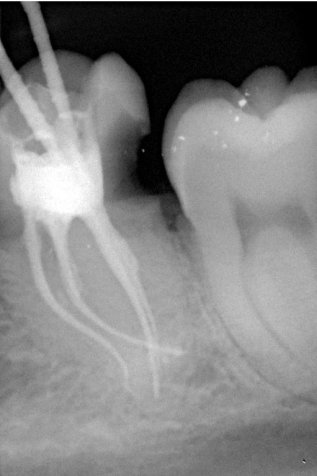

Fallbeispiel für eine unvollständige Wurzelfüllung

nach Revision und dichtem Verschluss